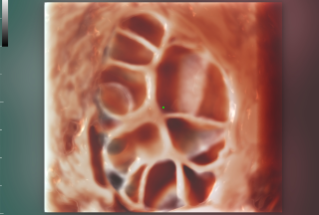

During their visit, the Southeast Asian delegation delved into in-depth discussions on the Standardized Chinese Ultrasound Training System and the Advancements in Pelvic Floor Ultrasound Technology with the experts from the West China Second Hospital of Sichuan University. These guests commended the Chinese ultrasound training system for its "remarkable reference value" and were impressed by the well-established development of pelvic ultrasound technologies in China, supported by extensive multi-center projects. Many experts also expressed their enthusiasm for future collaborations to undertake similar multi-center research projects with Mindray.